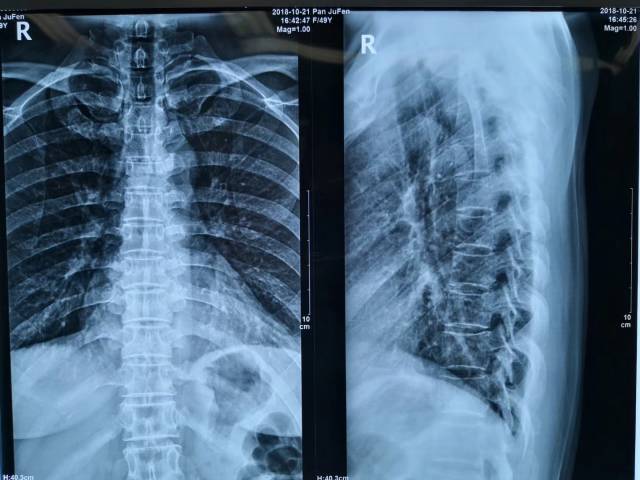

胸椎正侧位

胸椎正侧位像显示t8椎体变扁

胸椎正侧位x线:提示胸8,9骨折脱位,胸5,6,7椎体骨折.